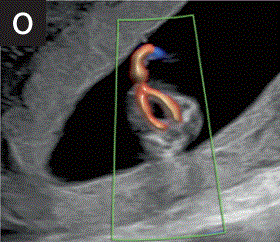

6.4 彩色多普勒有助于确认在舒张期存在两个不同的心室,并有助于排除明显的房室瓣反流(图2k)。

胎儿mt是什么检查什么疼吗【文献学习/规范指南】ISUOG实践指南(2023更新): 11-14周胎儿超声检查(全文)_https://www.jmylbn.com_新闻资讯_第18张

2 11+0至14+0周时,可作为详细胎儿超声检查的一部分获得的解剖图。

(k)采用彩色多普勒检查的胎儿心脏四腔切面,显示舒张压流分别从左右心房进入右心室和左心室。